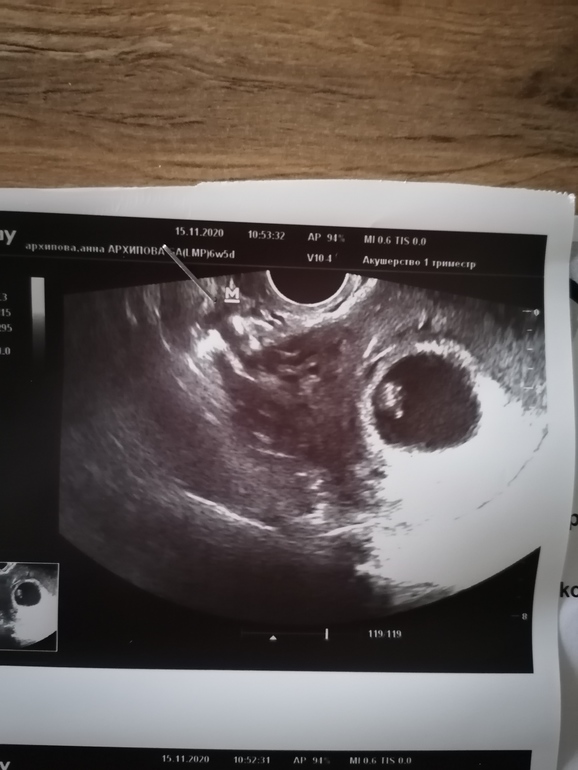

Как же я с утра понервничала, никогда ничего подобного не было, даже когда была ЗБ. Всегда с выделениями все отлично, а тут утром мазня коричнево-сукровичная. Проснулась от того, что сильно болела поясница, потом и живот поднывать стал. Моя врач сказали вызывать скорую и ехать на сохранение, выделения я ей показала. Но я решила не ехать, выпила транексам, ношпу и свечку вставила. Дюфастон не пью, т. к. прогестерон очень высокий 216. Выделений больше не было. Но решили с мужем сходить все же на узи, моя врач не принимала, пошла в другую клиники, а другому врачу. По УЗИ нет ни о слойки, ни тонуса. Шейка и все остальное закрыто, от куда выделения хрен знает. Врач сказала, перед сном выпить ещё 1 таблетку транексама и наблюдать, если не дай бог опять будет мазать, то в больницу. Теперь лежу дому и не шевелюсь. Молюсь что бы все было хорошо🙏🙏🙏🥰.

Ну и колобочек мой за 2 дня уменьшился, а не вырос🙈. Но думаю это погрешности измерения, да и аппараты разные и настройки разные. Видно, что явно больше стал, даже шевеления были видны и мне включили сердечко🥰🥰🥰💙💙💙. Такой бух-бух-бух был😍😍😍.

Вообщем сегодня по УЗИ пацан 200%%% и сердечко 134 удара. Может в прошлый раз тонусом его так сдачило, а тут ровное яичко.